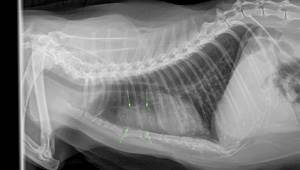

Врач проводит полное физикальное обследование пациента, подробно опрашивает владельца о симптомах. При выявлении хрипов, патологических шумов во время аускультации легких проводится рентгенография грудной клетки. На снимках, как правило, хорошо визуализируются опухолевые массы, свободная жидкость.